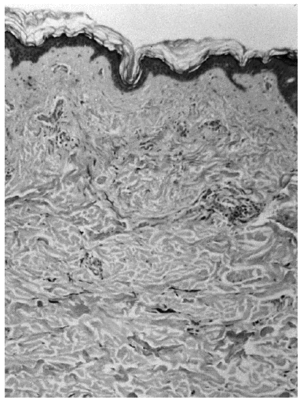

Presentaba una mácula hiperpigmentada de coloración azul-violácea y aspecto moteado que abarcaba la región interescapular. La lesión tenía unos bordes uniformes y bien delimitados (fig. 1). El resto de la exploración dermatológica no ofrecía ninguna otra lesión de interés. Se procedió a la realización de una biopsia cutánea que reveló una epidermis y una dermis normales salvo por la presencia en dermis reticular de células ovaladas, fusiformes y alargadas con intensa pigmentación melánica y algunas ramificaciones (figs. 2 y 3). Se efectuó una tinción con rojo Congo que resultó negativa. Las tinciones inmunohistoquímicas para proteína S100 y HMB 45 demostraron positividad de esas células. En la microscopia electrónica se pudo confirmar la presencia de melanocitos dérmicos. Debido a las dificultades para desparafinar la pieza no fue posible determinar la presencia de vaina extracelular melanocítica debido a la deficiente calidad de las imágenes.

Fig. 2. Panorámica histológica con melanocitos aislados en dermis reticular.